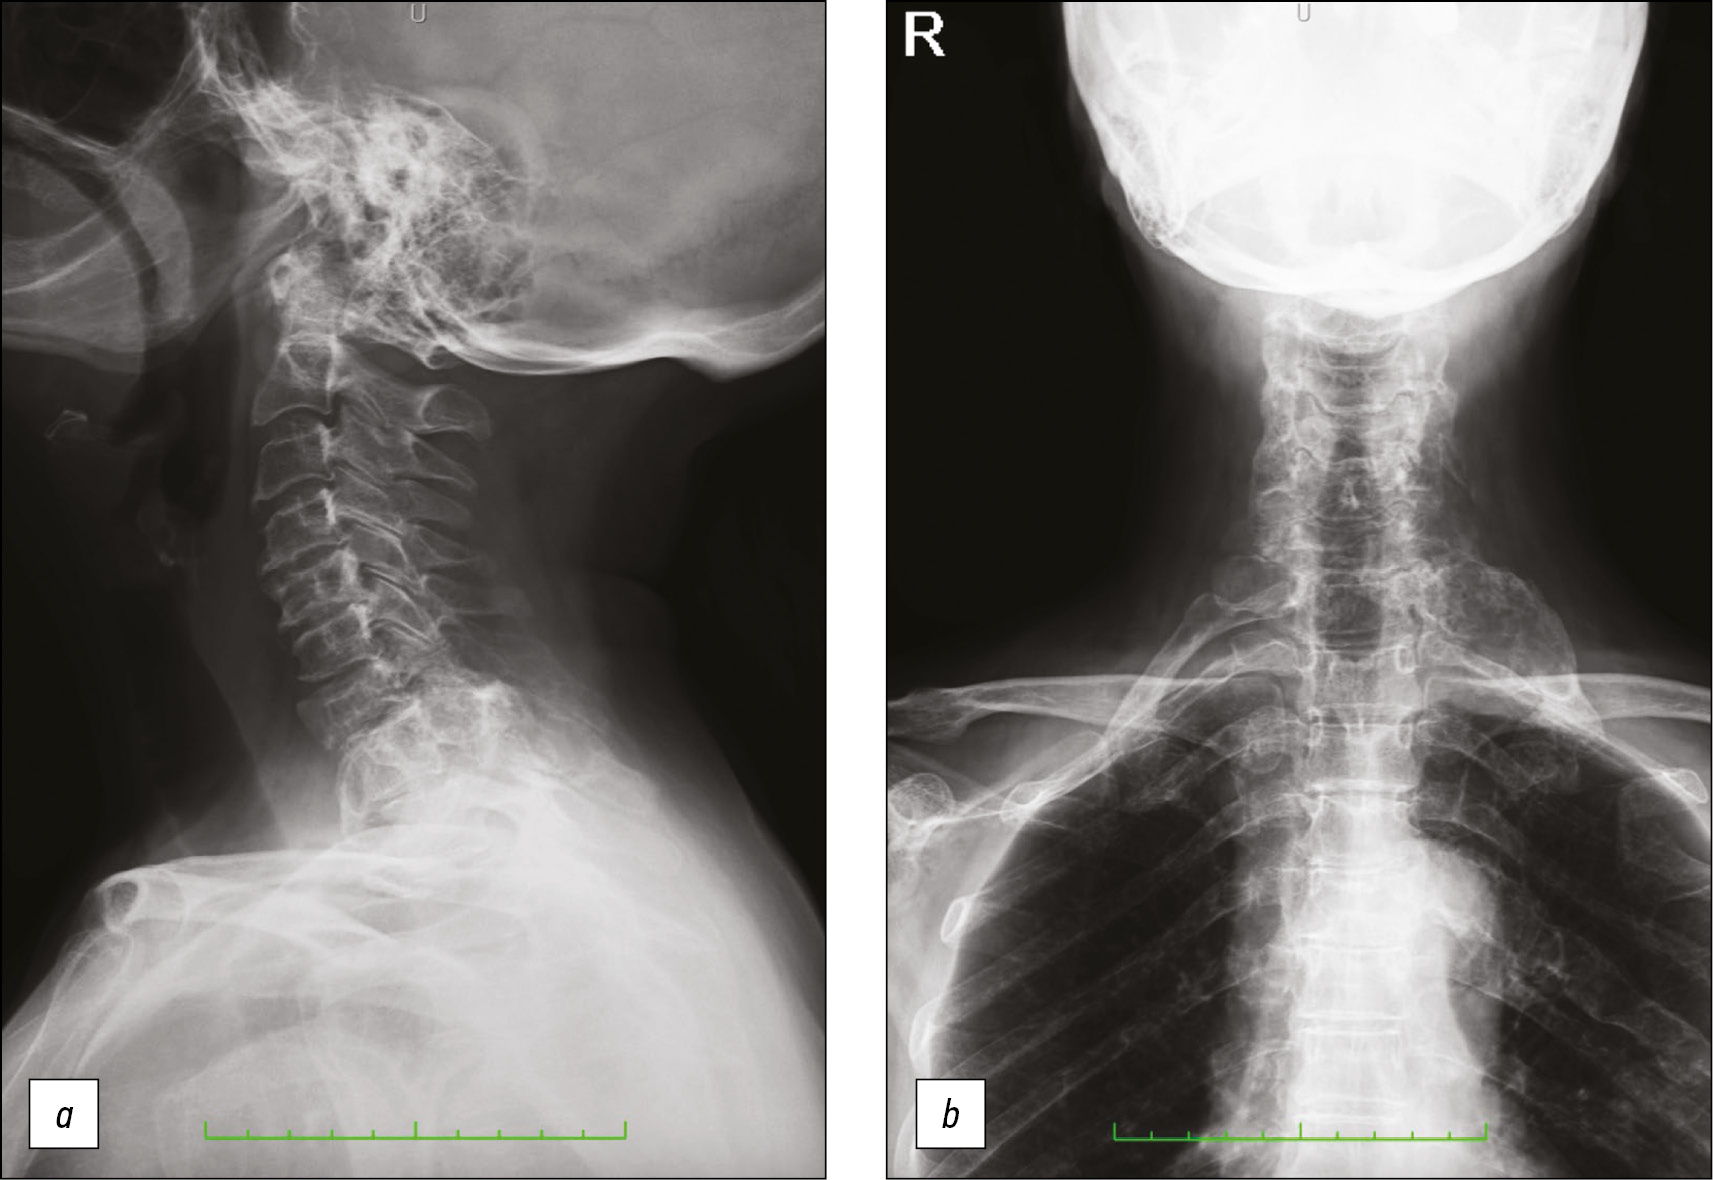

X-ray imaging showed the presence of well-circumscribed lytic lesions at the level of C5, C7, and D1 vertebrae and at the posterior arch of the fifth left rib, together with a larger localization of the disease at the first left rib’s posterior arch, which presented a bubbly cystic bone lesion with a cortical “blown appearance”, cortical thinning, and none periosteal reaction (Fig. 1).

Fig. 1. The cervical tract X-ray, in the context of a diffused uncovertebral arthrosis, shows the presence of some ill-defined lithic bony lesions at C5, C7, and D1 vertebrae (a) and the posterior arch of the fifth left rib (b); moreover, a 5.5 × 2.5 cm expansile lesion of the posterior first left rib is visible, with a swollen and blown cortical appearance (b).